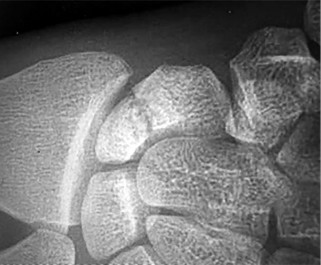

- الأشعة السينية (X-rays): هي الخطوة الأولى في تقييم الكسور، الخلوع، وتغيرات التهاب المفاصل. تساعد في تحديد مدى تدهور العظام والمسافات المفصلية. على سبيل المثال، تُظهر صور الأشعة السينية كسور السلاميات

أو كسور قاعدة العظم المشطي الخامس